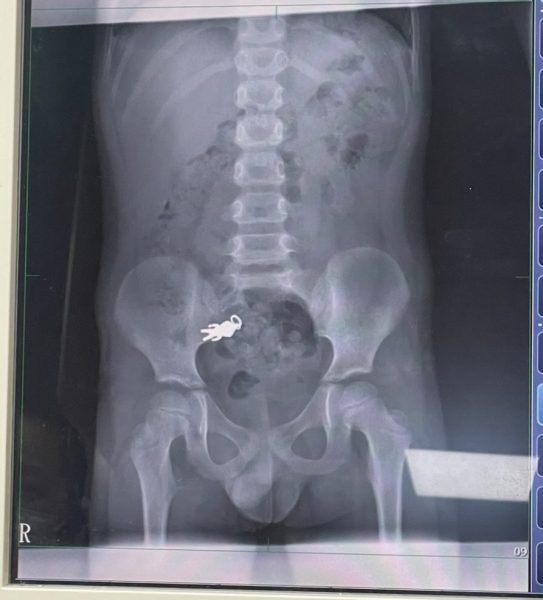

X-ray shows keychain in boy’s intestines

The X-ray clearly showed the keychain — measuring about 2.8cm by 1.4cm — inside his intestines, sparking amused reactions from netizens.